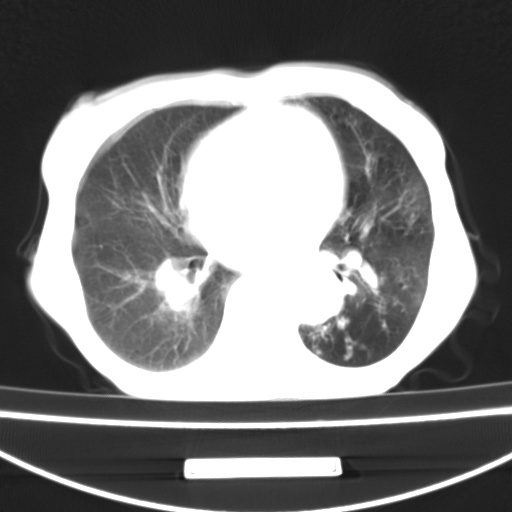

患者 女 67岁,反复咳嗽咳痰2年,加重伴喘及双下肢浮肿1月

诸大血管及f肺门血管增粗迂曲.左下肺多发薄壁空腔影.部分非也透亮度增高.薄曾扫描可区分肺气肿类型.考虑1.慢性支气管炎 2.左下肺支气管扩张 3.肺气肿 4 肺动脉高压5.是否有先心病病史

考虑1.慢性支气管炎 2.左下肺支气管扩张 3.肺气肿 4 肺动脉高压

慢支炎、肺气肿、双肺感染、左下囊状支扩。

慢支、肺气肿、肺动脉高压;左下肺囊状支扩并粘液栓形成。